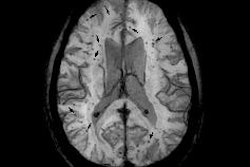

Researchers used susceptibility-weighted MRI (SWI-MRI) to evaluate 603 military personnel with TBI at Walter Reed National Military Medical Center. They found that nearly a quarter of the patients had evidence of cerebral microhemorrhages within three months of their injury, but the number with detected bleeds fell in the months afterward.

Two radiologists independently reviewed the results and agreed on the findings in 41 (95%) of the 43 patients with microhemorrhages. With SWI, they detected 585 microhemorrhages in 37 patients, compared with 362 microhemorrhages at GRE imaging.

SWI also detected significantly more cerebral microhemorrhages per patient (17.7 ± 20.7) than GRE (11.0 ± 12.6). Most microhemorrhages (451/585, or 77%) appeared more conspicuous on SWI than GRE images, and the greatest number of microhemorrhages were found in the frontal subcortical regions (174, or 30%), followed by the parietal subcortical region (87, or 15%) and the temporal subcortical region (79, or 14%).

Additionally, the sooner an injured solider received an MRI, the greater the chance of finding cerebral microbleeding. SWI detected microhemorrhages in 24% of patients who underwent imaging within three months after their injury, compared with 18.4% for those scanned after three to six months, 7.6% for those scanned six to 12 months later, and 5.2% for those scanned more than a year later. The effect could be due to changes in iron deposits in the brain over time, making it more difficult to detect the microhemorrhages, according to the authors.